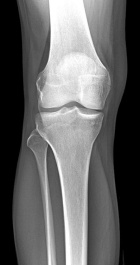

Patient is a 45 y/o Ortho nurse who presented w/ enlarging painful R. knee mass for past year; PMH: ovarian cysts s/p rupture

PE: R. knee w/ well circumscribed mass at the lat. aspect of the patella; + tenderness to palpation; normal PROM; NVI

Zoom image: Radiological image Radiological image.